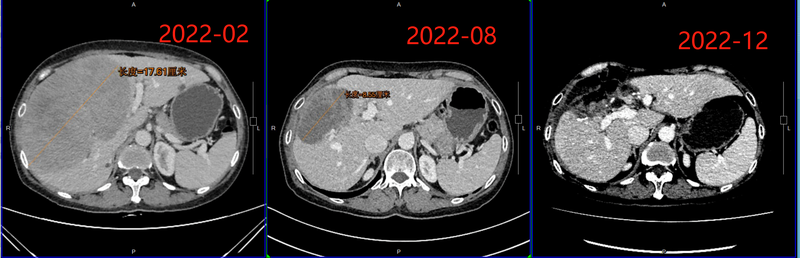

圖上患者2021年底發(fā)現(xiàn)肝內(nèi)巨大占位并盆腔占位,在當(dāng)?shù)刂磺谐伺枨徊≡?,病理提示為直腸NETG2。到我門診就診后行PETCT雙掃描和增強(qiáng)CT等檢查,發(fā)現(xiàn)肝內(nèi)巨大轉(zhuǎn)移瘤,最大直徑18厘米多,邊界很清楚。在多學(xué)科討論后指定方案:先行介入肝動(dòng)脈栓塞TAE術(shù),減瘤后再行外科處理,全身治療為SSA。經(jīng)我團(tuán)隊(duì)完成4次精細(xì)TAE后,病灶縮小至8厘米。內(nèi)部大量壞死。后于2022年11月13日由殷曉煜院長(zhǎng)主刀行機(jī)器人輔助中肝切除,完美切除肝轉(zhuǎn)移瘤。目前到達(dá)無(wú)瘤狀態(tài)。神經(jīng)內(nèi)分泌腫瘤肝轉(zhuǎn)移一定要盡早行TAE等肝臟局部治療減瘤,不要到用了很多線治療才把TAE等介入方法當(dāng)做救命稻草。介入+全身治療+外科切除這一套組合拳用得好,團(tuán)隊(duì)給力!這就是中山大學(xué)附屬第一醫(yī)院NET多學(xué)科團(tuán)隊(duì)!膽胰外科殷曉煜院長(zhǎng)周二特需門診消化內(nèi)科張寧教授周四下午門診我周二下午(腫瘤介入教授門診)周三上午(腫瘤介入教授門診2)。